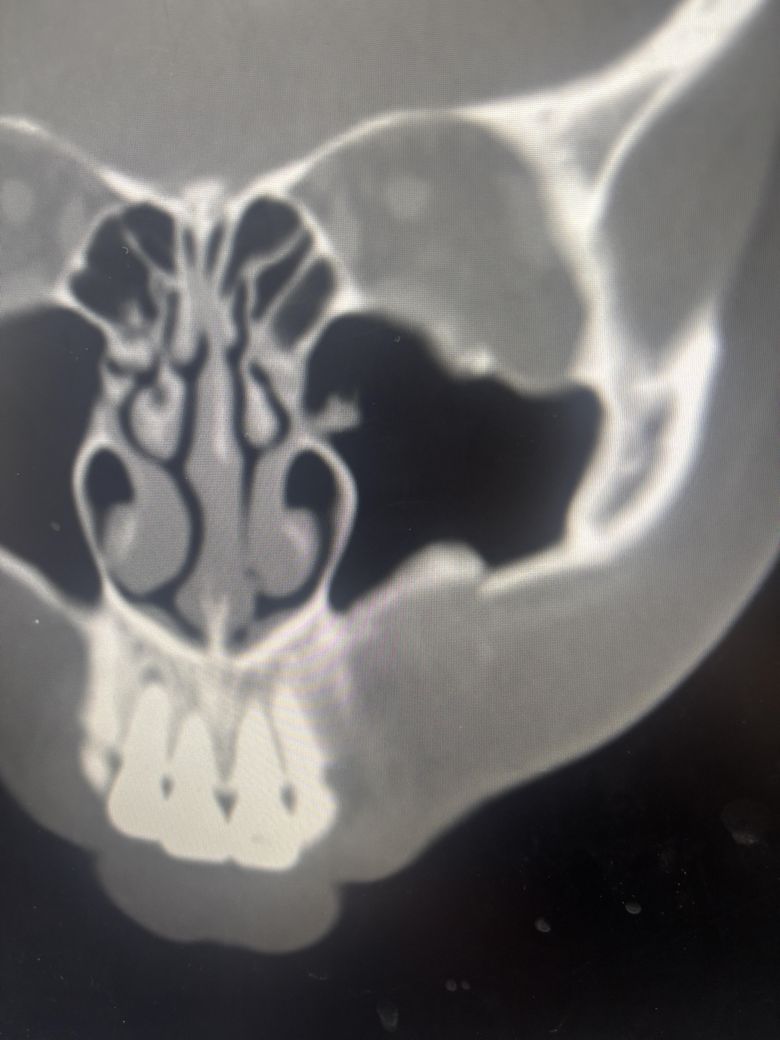

• 2번 째 사진

폭행으로 인해 코 골절 / 위턱 골절 판정을 받았는데

턱은 골절된 부분이 너무 심하지 않아서 그냥

자연치유 하면 된다고 진료를 받았습니다

윗턱 부분도 그냥 나두면 알아서 붙는 그런 상태일까요 ? 일단 수술은 대학병원 성형외과 / 종합병원 성형외과 두군대 가볼려고 합니다